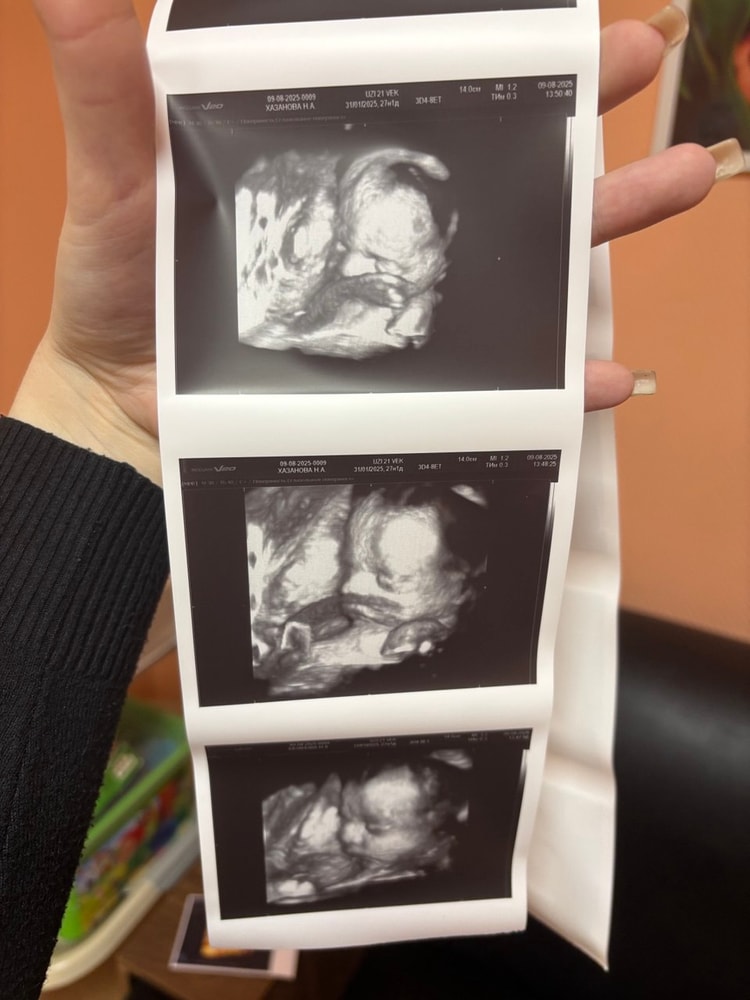

УЗИ, КТГ, доплерВ субботу ходили на 4Д УЗИ. Срок на этот момент без одного дня 25 недель. Неудачно лежал, конечно, но рассмотреть все таки удалось)) И нам подтвердили пол, так как всего 1 раз смотрели на УЗИ, а ведь всякое бывает. По началу малыш вел себя спокойно, а под конец вообще потянулся и закрылся ручками, но мы успели его более-менее рассмотреть до этого момента. Носик прям мужа 100-процентный, остальное так и не разобрали где чье, да и не так важно. Эмоции у меня прям зашкаливали, а вот мужу не зашло. Крипота, говорит, ахаха. Я отчасти согласна, выглядит это и правда жутковато, но когда понимаешь, что это твой малыш, то все эти моменты на второй план уходят. Записали нам видео всего процесса, наделали много ч/б фоточек и 1 сделали цветную. Вот такой богатырек у нас подрастает))